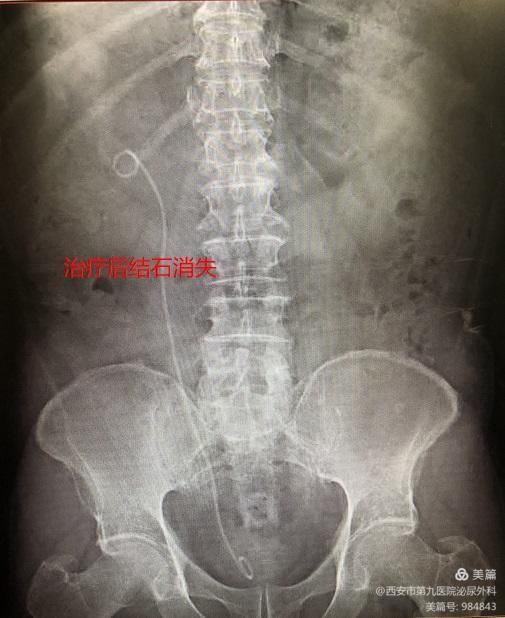

75岁男性患者张某,因右侧肾绞痛在泌尿外科诊断为右肾多发结石(4枚),于2月于在科室行右肾结石输尿管软镜下钬激光碎石术,术后已康复出院

术前结石如上图,右肾多发结石